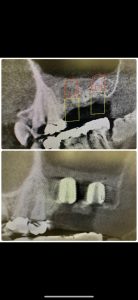

次は、インプラント定期検診

安定!💪

画像見れば変遷がなんとなくわかる

詳細は割愛

患者さんの、Q OLを下げない為に色々試行錯誤してます